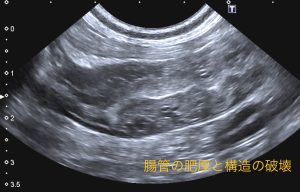

超音波検査を行ったところ、回腸から盲腸、結腸にかけて腸の肥厚と構造の破壊が認められました。腫瘍の可能性も考慮されたため、CT検査と手術(回盲部切除)を行いました。

病理組織学的検査では、リンパ液漏出に伴う肉芽腫性腸炎と診断されました。今後は、食事管理、内科治療が継続的に必要で、再発にも注意が必要です。